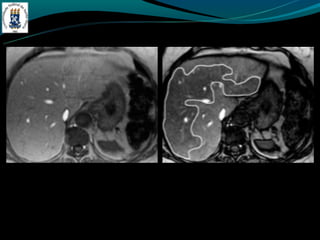

-RM: trombo agudo hiper em T1 e T2, crônico hipo em T1 e

hiper em T2.

TROMBOSE DA VEIAPORTA -Complicação de cirrose -Invasão ou compressão tumoral -Hipercoagulabilidade -Inflamação -Incidência de 5% na hipertensão portal e próximo de 30% no CHC -TC: Esplenomegalia, formação de colaterais, ascite, e pode ter alta atenuação na fase arterial. -RM: trombo agudo hiper em T1 e T2, crônico hipo em T1 e hiper em T2.